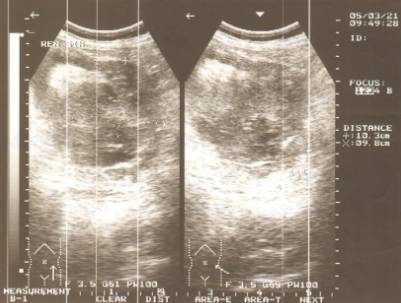

нирок з неоднорідною структурою, контри їх ставали більш чіткими. В наступні

3-4 доби гематоми збільшувались до своїх максимальних розмірів, візуалізувалися

як рідинні утворення з нечіткими контурами гіпоехогенної однорідної або

неоднорідної структури (рис. 2).

Рис. 2. Підкапсульна гематома в

проекції нижнього полюсу лівої нирки через 5 діб після травми. В-режим.